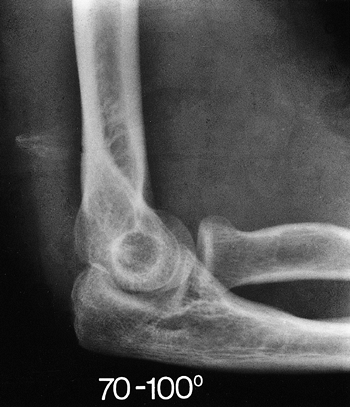

was treated in a cast for 3 weeks and developed a contracture from 70

to 100 degrees (Fig. 21-10). After release the arc improved

from 20 to 125 degrees (Fig. 21-11). There was no pain and the patient was pleased with the outcome.

Figure 21-10. Marked contracture developed after 3 weeks immobilization for “simple” dislocation. The joint is intact.